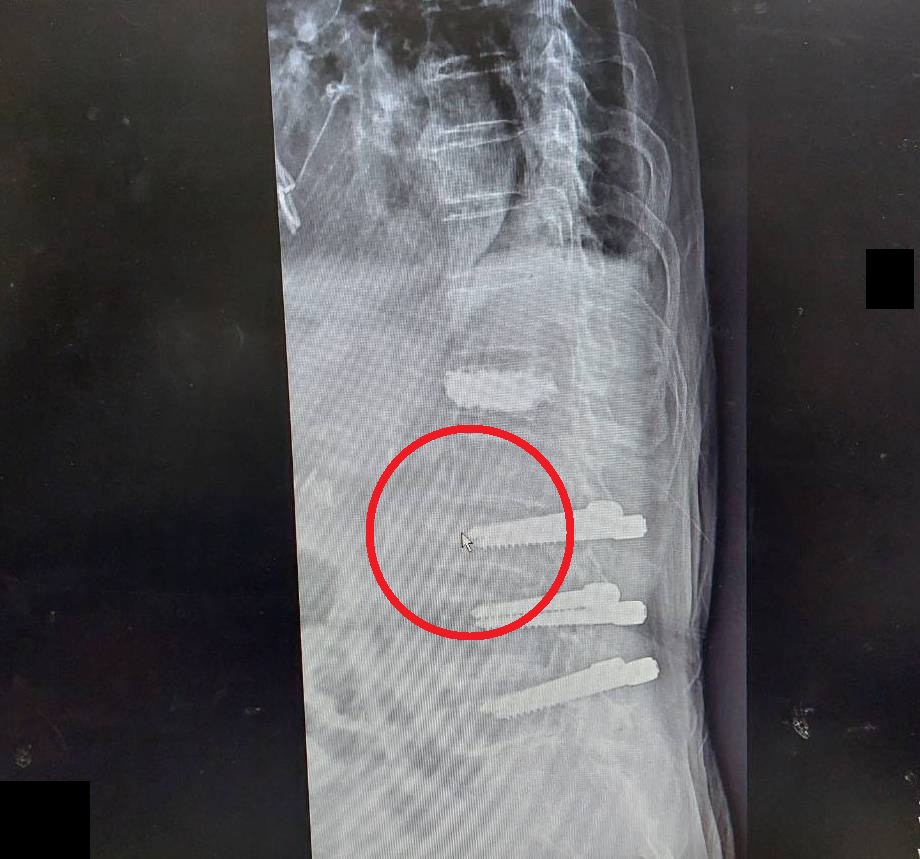

容志雄醫師分享近日治療的兩個案例,一是高齡93歲的奶奶,過去脊椎第3、4、5節曾手術打鋼釘,此次受傷剛好是在第3節上緣,評估病人因個子較高,加上第一支鋼釘打入的位置較往下一些,因此利用上緣狹小的空間,順利完成灌骨泥治療。第二位病人是82歲的奶奶,個子嬌小且鋼釘位置打得很好,能打入骨泥的空間更小,所幸在使用孩童專用的細小鋼針後,也成功灌入骨泥,解決壓迫性骨折的疼痛。兩位病人的困難度都相當高,所幸在手術過程中透過C型臂X光機準確的定位,及醫師專業的判斷,才能在非常狹窄的空間下,精準地將骨泥灌入受傷位置。

93歲奶奶受傷位置在第3節上緣(紅圈箭頭處),醫師利用狹小的空間完成手術。